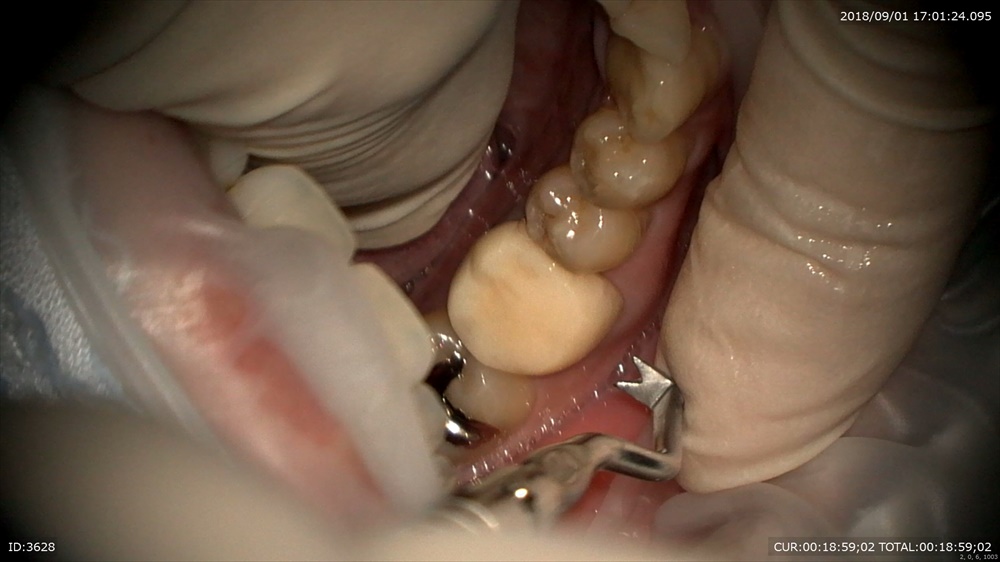

今日の患者さん。この方は他院の根管治療後腫れて治らず今年の年始にいらして頂きました。

歯科ドックの結果

歯周病治療、根管治療、土台、被せ物のやり直しが必要でした。

細かく根管治療

手間ヒマかけて

23倍でバイオフィルムを取り

土台をたて

仮歯で半年様子見

初診の腫れも消え症状もなく、患者さん

「抜歯しなくて良いのですね」

と喜んでいました。

歯周病治療後型取りをして

本日セット 技工士間中先生

少しの段差もありません、

このように重症の虫歯でも抜歯せずに治療ができます。ただし、